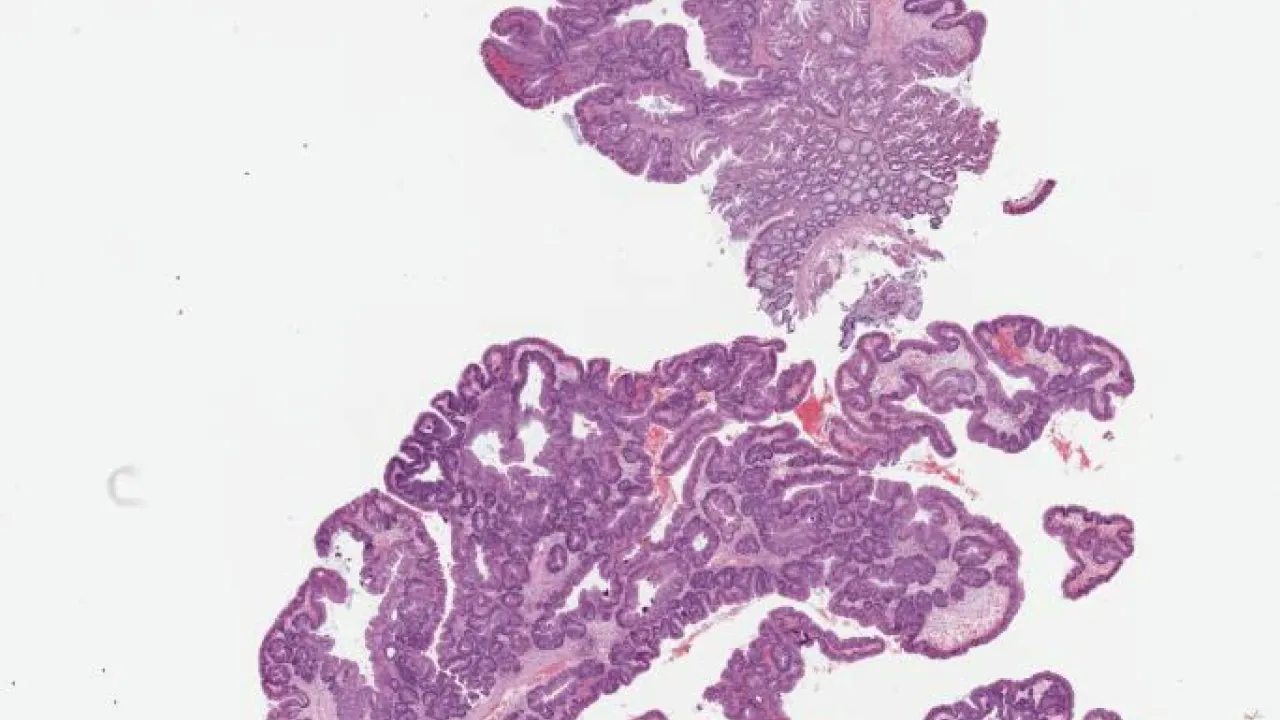

Kidney, Papillary renal cell carcinoma